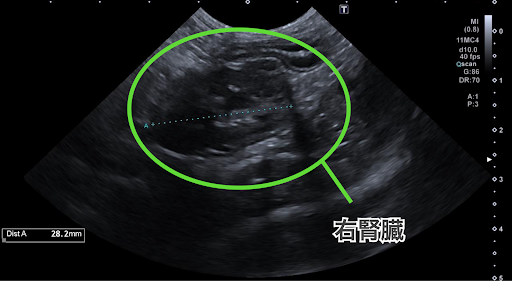

定期的な健康診断を行ったところ、エコー検査で右腎臓に腫瘍が確認されました。

こちらがエコー検査の画像です。